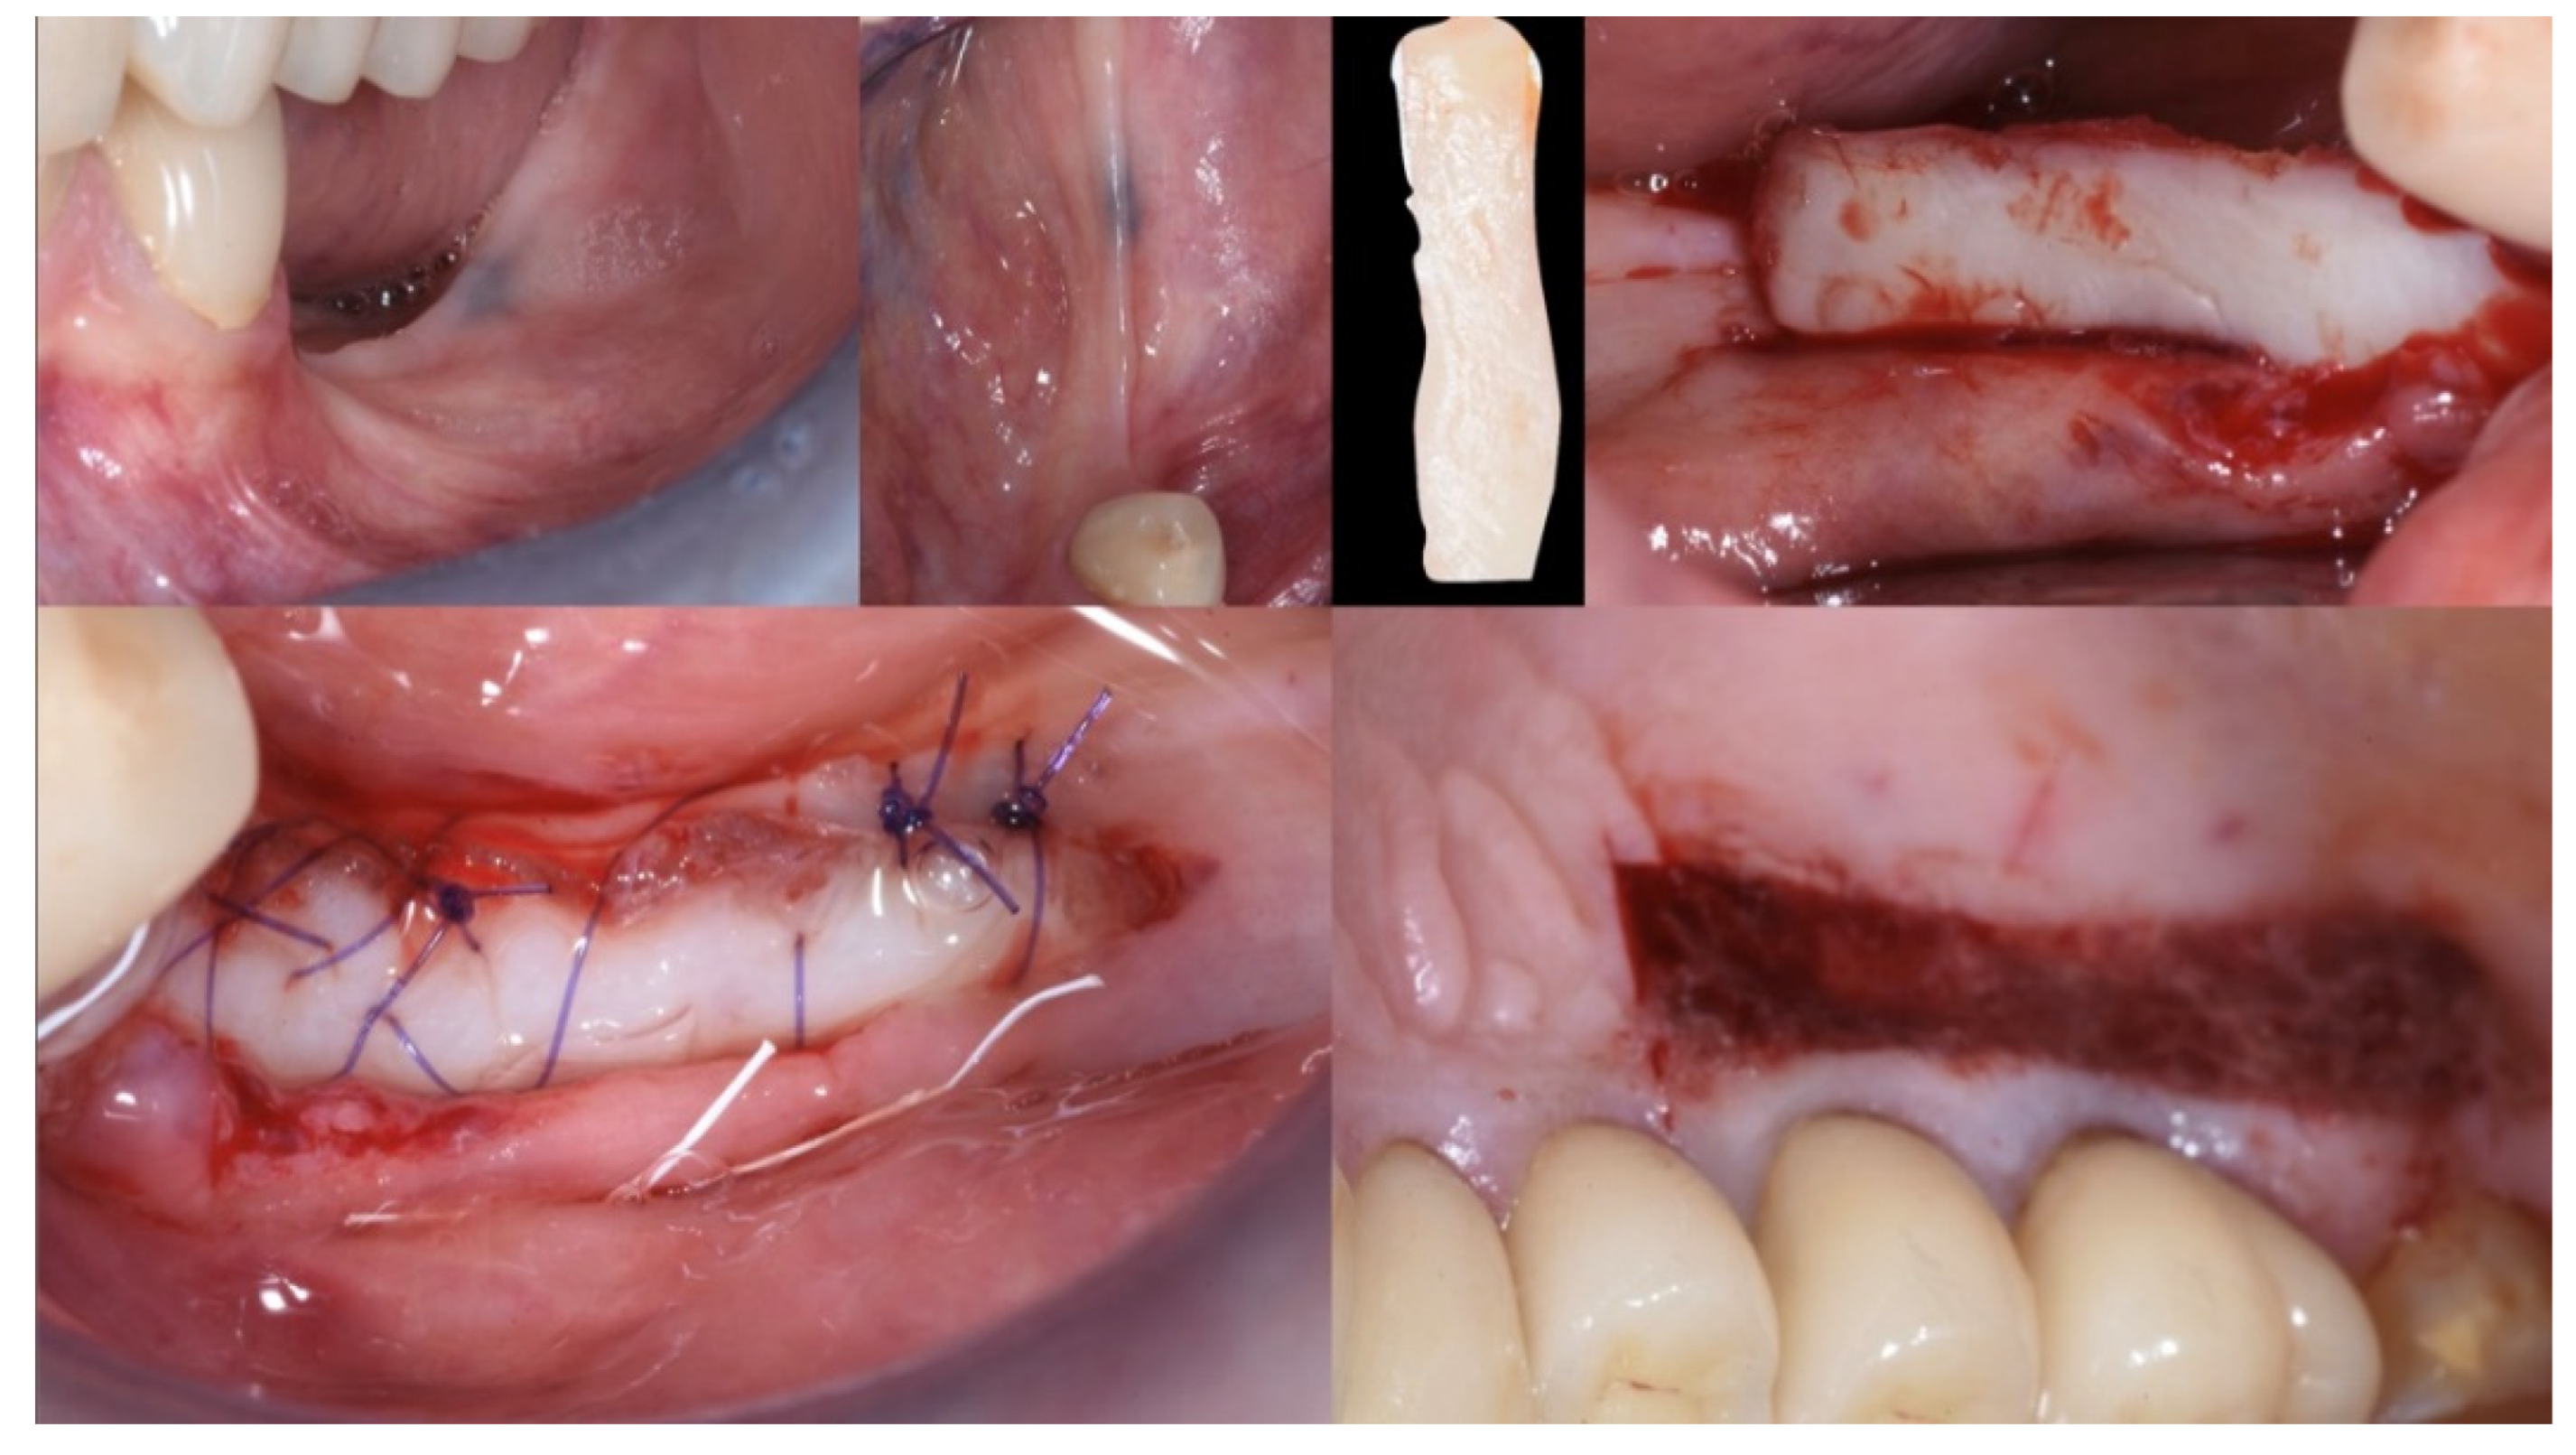

Figure 4.

Mucogingival surgery. A free gingival graft was used to enhance both the quality and quantity of the soft tissue of the edentulous ridge.

Three months after surgery, the graft showed a healthy color and optimal integration into the surrounding tissues. The mucogingival surgery provided good protection for the subsequent hard tissue regeneration (Figure 5).

Figure 5.

Soft tissue healing at three months.